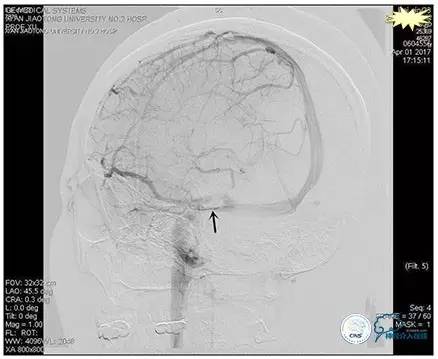

右侧ICA正位

右侧ICA侧位

右侧ICA斜位

左侧ICA正侧位

右侧VA正位

左侧VA正侧位

术中造影

5ml/s,总量8ml,压力100~150